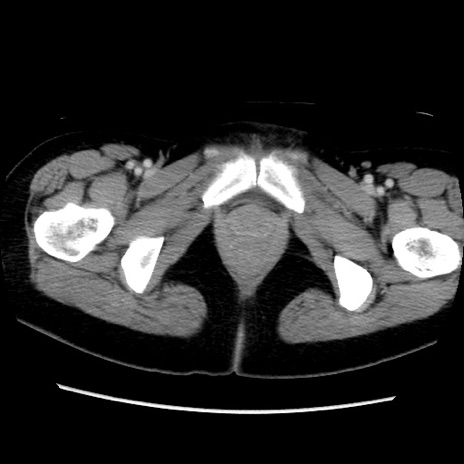

MRI(4日後)

【症例】40歳代女性

【主訴】上下腹部痛

【現病歴】2日目から下腹部痛あり。夜間は痛みで眠れなかった。昨日より上腹部痛と下痢が出現。臥位で痛みは軽快したため、休んでいた。本日になって臥位でも立位でも痛みが強くなってきたため救急要請。

【既往歴】子宮内膜症

【身体所見】部:平坦・軟、左上下腹部に圧痛あり、反跳痛あり。

【データ】WBC 21800、CRP 26.78